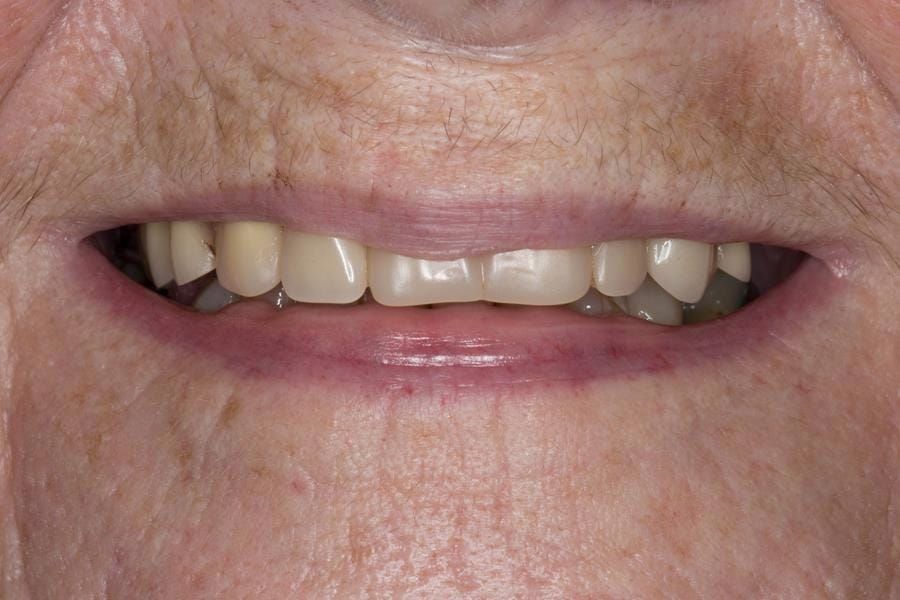

The 'gasket' or 'window' denture - provision of a maxillary cobalt chromium based partial denture

- Poorly fitting cobalt chromium based maxillary partial denture, which has been added to. This exhibited poor retention, stability and tissue fit (support). Unable to wear a new acrylic based denture.

Following consultation and second discussion appointment the patient chose to have option 2 namely, a window denture - maxillary cobalt chromium based partial denture. The clinical situation and treatment process is shown in detail below with photographs. The patient was successfully rehabilitated with this and her quality of life considerably improved. The clinical work was provided by Finlay and the technical work by Rowan.